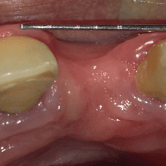

Falta de hueso para implantes

La falta de hueso suficiente para la colocación de implantes puede ser una barrera para el tratamiento.

Los pacientes pueden ser informados de que no tienen suficiente hueso en la mandíbula o el maxilar para soportar un implante.

El tratamiento incluye técnicas de regeneración ósea, como injertos óseos, para aumentar el volumen óseo.